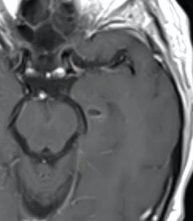

Glioblastome

Decouverte fortuite aux urgences, Confirmé a la patho

Decouverte fortuite aux urgences, Confirmé a la patho